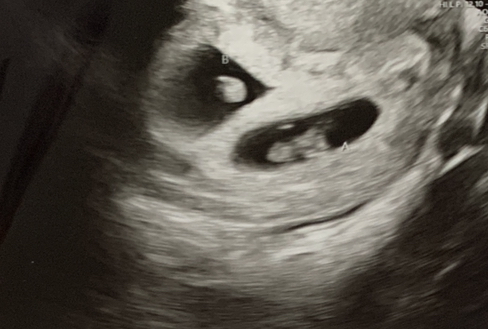

Back with some new ultrasound pics! 12w3d here :)

Attachment 42687

Attachment 42688

Attachment 42689

Attachment 42690